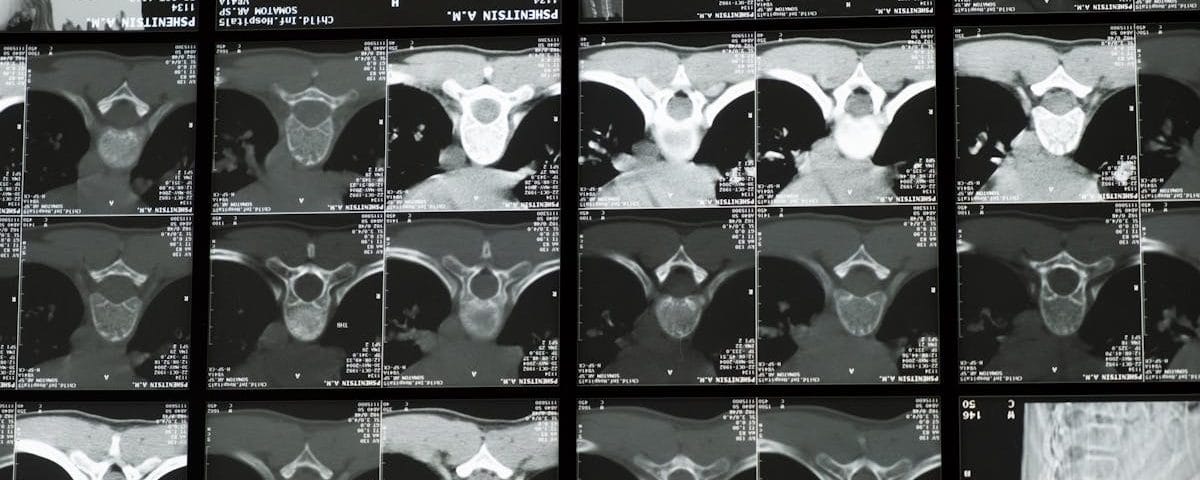

Une IRM ou une radiographie est souvent recommandée pour évaluer l’état de la colonne vertébrale.

Quels examens permettent de diagnostiquer un pincement discal?

Une IRM ou une radiographie est souvent utilisée pour confirmer le diagnostic d’un pincement discal ou d’un disque écrasé.